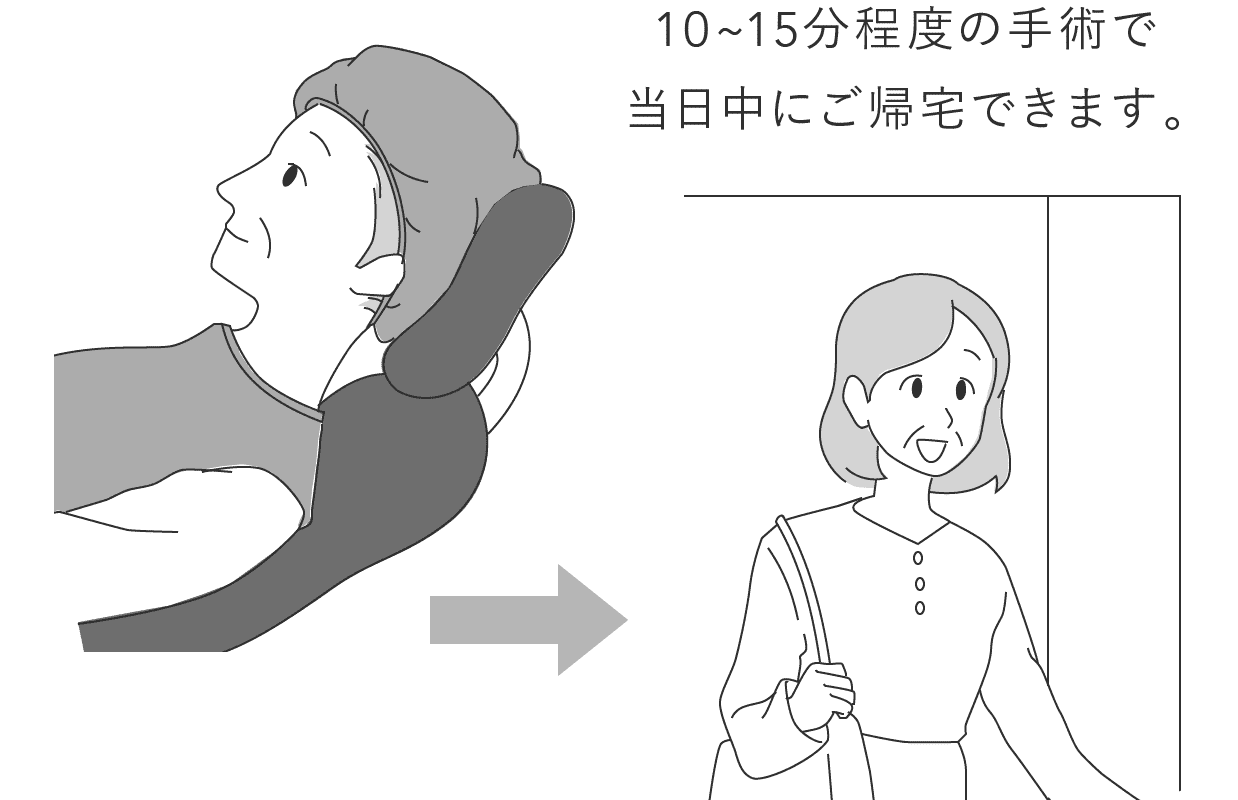

手術と聞くと大掛かりに思えるかもしれませんが、技術の進歩により今では多くの医療機関で日帰りで実施されています。

当院の白内障手術も、日帰りにて承っております。

白内障手術の時間は片眼で通常15〜20分です。

手術時間は片目で通常15分〜20分で、術前の準備や術後の安静時間を含めると3〜4時間ほどになります。

手術方法や麻酔の進歩により、手術後すぐに起き上がり、歩くことができます。